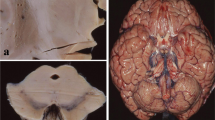

Quantitative analysis of LBHIs in the pons including the facial nucleus

For histological analyses of the facial nucleus (nVII), we examined non-transgenic littermates (n=3, 264±7 days) and G1L mice in the moribund state (n=7, 258±7 days). Each carefully hemisected brainstem was embedded in paraffin and sectioned transversely. The pons including the nVII was identified in these sections, with reference to the mouse brain atlas of Paxinos and Franklin [37]. Six-micrometer-thick paraffin sections were prepared and stained with HE. In the nVII, large neurons with clear nucleoli and cell bodies were counted. LBHIs located in three subregions of the pons (vacuole-rich area = intra-nVII, the border zone, and vacuole-poor area, as delineated in Fig. 1) were also counted (×40 objective). To estimate the number of LBHIs per unit area in each subregion, video images of the pons were obtained with a digital camera (KEYENCE VB-7010, KEYENCE, Osaka, Japan) attached to a light microscope (ECLIPSE E800, Nikon, Tokyo, Japan) for each section, and the areas of three subregions were measured using image analysis software (VH-H1A5, KEYENCE). Every fifth section (at 24-μm intervals) was obtained, and three sections from each mouse were used to obtain the total number of neurons and the density of LBHIs. The number of motor neurons and the density of LBHIs were analyzed statistically. All quantitative investigations were performed independently by three neuropathologists (HS, HF, SK).

Schematic diagram of the three subregions in the pons; vacuole-rich area (=intra-nVII), the border zone and vacuole-poor area. The boundary of massive vacuole formation limited to the facial nucleus (nVII) is shown at low (a) and high (b) magnification as a yellow line, using actual microscopic fields digitized for illustrative purposes. The definition of the vacuole-rich area (=intra-nVII), border zone and vacuole-poor area is as follows: vacuole-rich area (light blue) corresponds to the inner area outlined in yellow; the border zone (white) corresponds to the surrounding area outlined in yellow and green, 120 μm exterior to the yellow line; the vacuole-poor area (pink) corresponds to the outer area of the pons excluding the other two regions. N neuron

Quantitative analysis of LBHIs in the nVII and the differential localization of LBHIs and vacuoles

HE staining revealed atrophic motor neurons with prominent vacuole formation in the nVII of moribund G1L mice. Most of the vacuoles in the nVII (Fig. 7b) were larger than those observed in the lumbar segment. The number of motor neurons in the nVII was significantly reduced (Table 2, P<0.05), and LBHIs were found only rarely in the vacuole-rich area (=intra-nVII). In marked contrast, LBHIs were found frequently in the border zone (see Materials and methods), but there were very few vacuoles (Fig. 7c). Most of the vacuoles were located in the neuropil, and not in the soma of neurons (Fig. 7d). Most of the LBHIs were also intra-neuritic. The LBHIs in the border zone were larger than those in the vacuole-rich area (=intra-nVII). Quantitative analysis of data from the three subregions of the pons demonstrated a preferential localization of LBHIs to the border zone, the area surrounding the nVII (Table 2, P<0.01).

Representative hematoxylin and eosin staining in the nVII of control (a; 261 days) and G1L (b–d; end stage) mice. a, b The number of motor neurons in the G1L nVII is reduced, and all of the residual neurons are atrophic in G1L mice as compared with the controls. Note the prominent vacuolization (arrow heads) and lack of LBHIs inside the G1L nVII. c Many LBHIs are present (arrows, white arrow) in the area surrounding the nVII. The yellow line delineates the vacuole-rich area (=intra-nVII). d A large LBHI (white arrow), more than 10 μm in diameter, is located in a neurite, and not in the soma. Scale bar a (also for b) 50 μm, c 100 μm, and d 20 μm